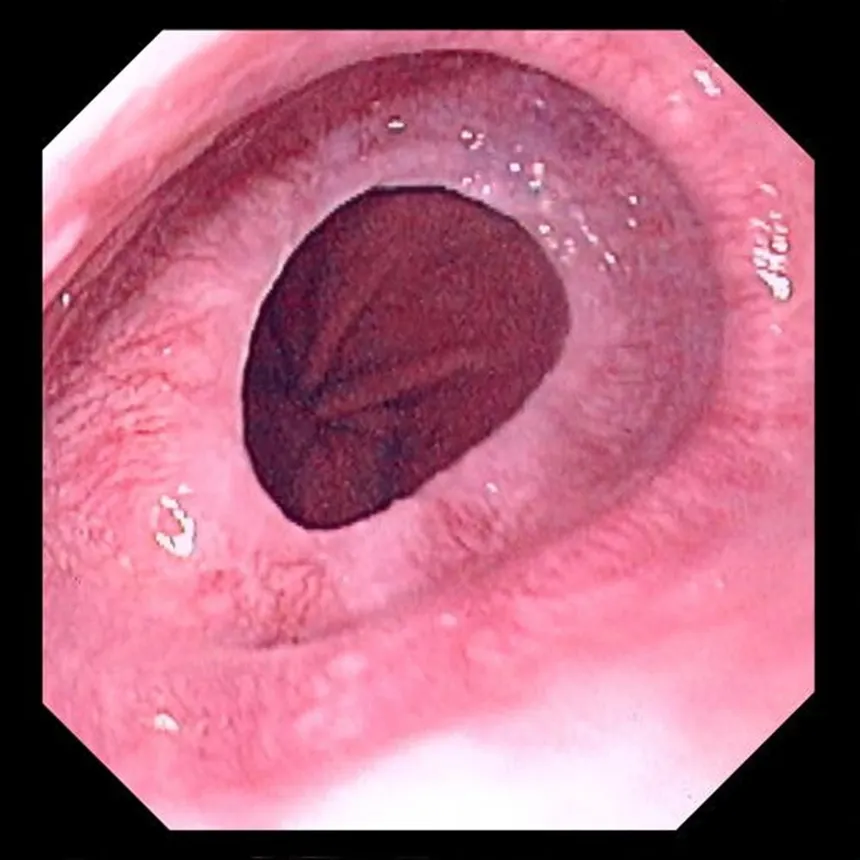

1) diagnostic

2) histologie

3) associations causale

1) oesophagite disséquante

2)

Couche superficielle de l’épithélium éosinophyle, pycnotique avec détachement

Couche plus profonde de l’épithélium normal avec inflammation parfois présente

3)

Médicaments

fumée

Maladies bulleuses

strictures